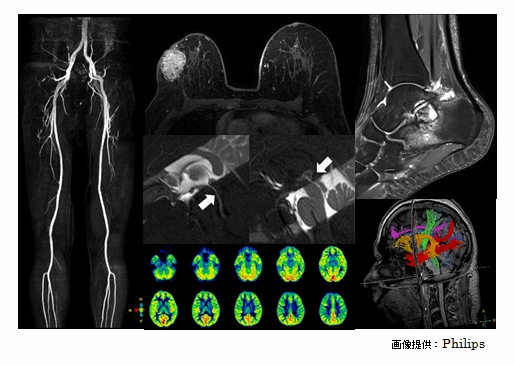

1.5T装置の約2倍の磁場強度

を持つ最新鋭のMRI装置です。

一般的な3.0T装置よりも

強い信号を得ることが

できるため、より高精細な

画像を撮像できます。

・頭部、腹部、四肢など幅広い領域の検査を行っています。

・脳機能検査・造影剤を用いない脳血流検査・脳神経画像・手術支援画像

などの特殊検査を行っています。

・造影剤を用いない心血管撮像を行っています。